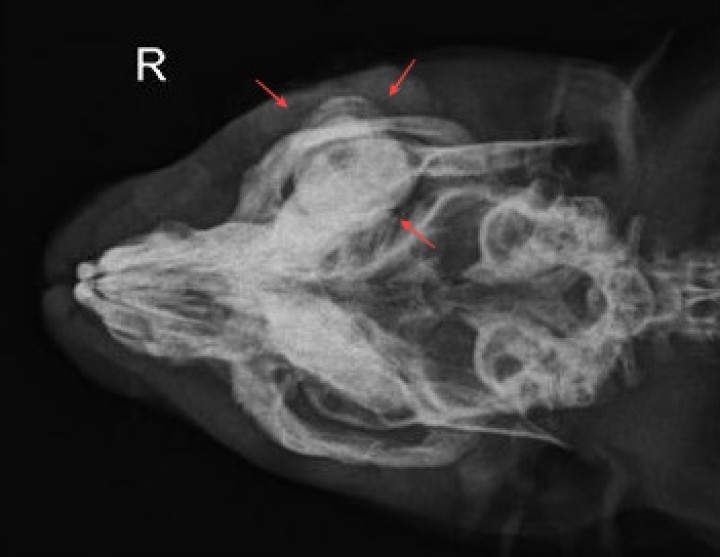

Debido al mal pronóstico de las lesiones en el globo ocular, se decidió realizar la enucleación del mismo. La analítica sanguínea prequirúrgica resultó normal. Se realizaron radiografías de cuerpo entero (sin alteraciones reseñables) y de cráneo, las cuales evidenciaron radiopacidad heterogénea del OD con silueta redondeada irregular (Figs. 4 y 5). El protocolo anestésico consistió en una combinación de midazolam 1 mg/kg IM (Midazolam Normon 15 mg/3ml Solución inyectable, Normon, Madrid), buprenorfina 0,03 mg/kg IM (Buprecare 0,3 mg/ml solución inyectable, Haupt Pharma Livron, Francia), ketamina 3 mg/kg IM (Anesketin 100 mg/ml solución inyectable, Dechra Veterinary Products SLU, Barcelona) y dexmedetomidina 0,05 mg/kg IM (Dexdomitor 0,5 mg/ml solución inyectable, Orion Corporation, Espoo). Se realizó la inducción mediante mascarilla con sevofluorano (Sevoflo 100% líquido, Zoetis, Bélgica) al 4% en oxígeno. El mantenimiento de la anestesia se realizó mediante mascarilla con sevofluorano al 2% en oxígeno. Se llevó a cabo la enucleación del globo ocular mediante el método transconjuntival. El animal se mantuvo estable durante todo el procedimiento quirúrgico y su recuperación postquirúrgica resultó sin complicaciones. Se procedió al alta del paciente con tratamiento ambulatorio consistente en marbofloxacino 5 mg/kg PO q24h durante 10 días (Efex 10 mg comprimidos, Ceva S.A., Barcelona), meloxicam oral 0,5 mg/kg PO q12h durante 7 días, ranitidina 2,5 mg/kg PO q12h durante 7 días (Ranitidina 25 mg/ml, formulación magistral) y alimentación forzada en caso necesario con papilla 10 ml/kg q4-6h (Critical Care Herbivores, Oxbow Animal Health, Omaha, EE.UU.).

<p>Radiografía dorsoventral del cráneo. Se observa imagen radiopaca en OD (flechas rojas) compatible con calcificación del globo ocular derecho.</p>

Figura 4

Radiografía dorsoventral del cráneo. Se observa imagen radiopaca en OD (flechas rojas) compatible con calcificación del globo ocular derecho.